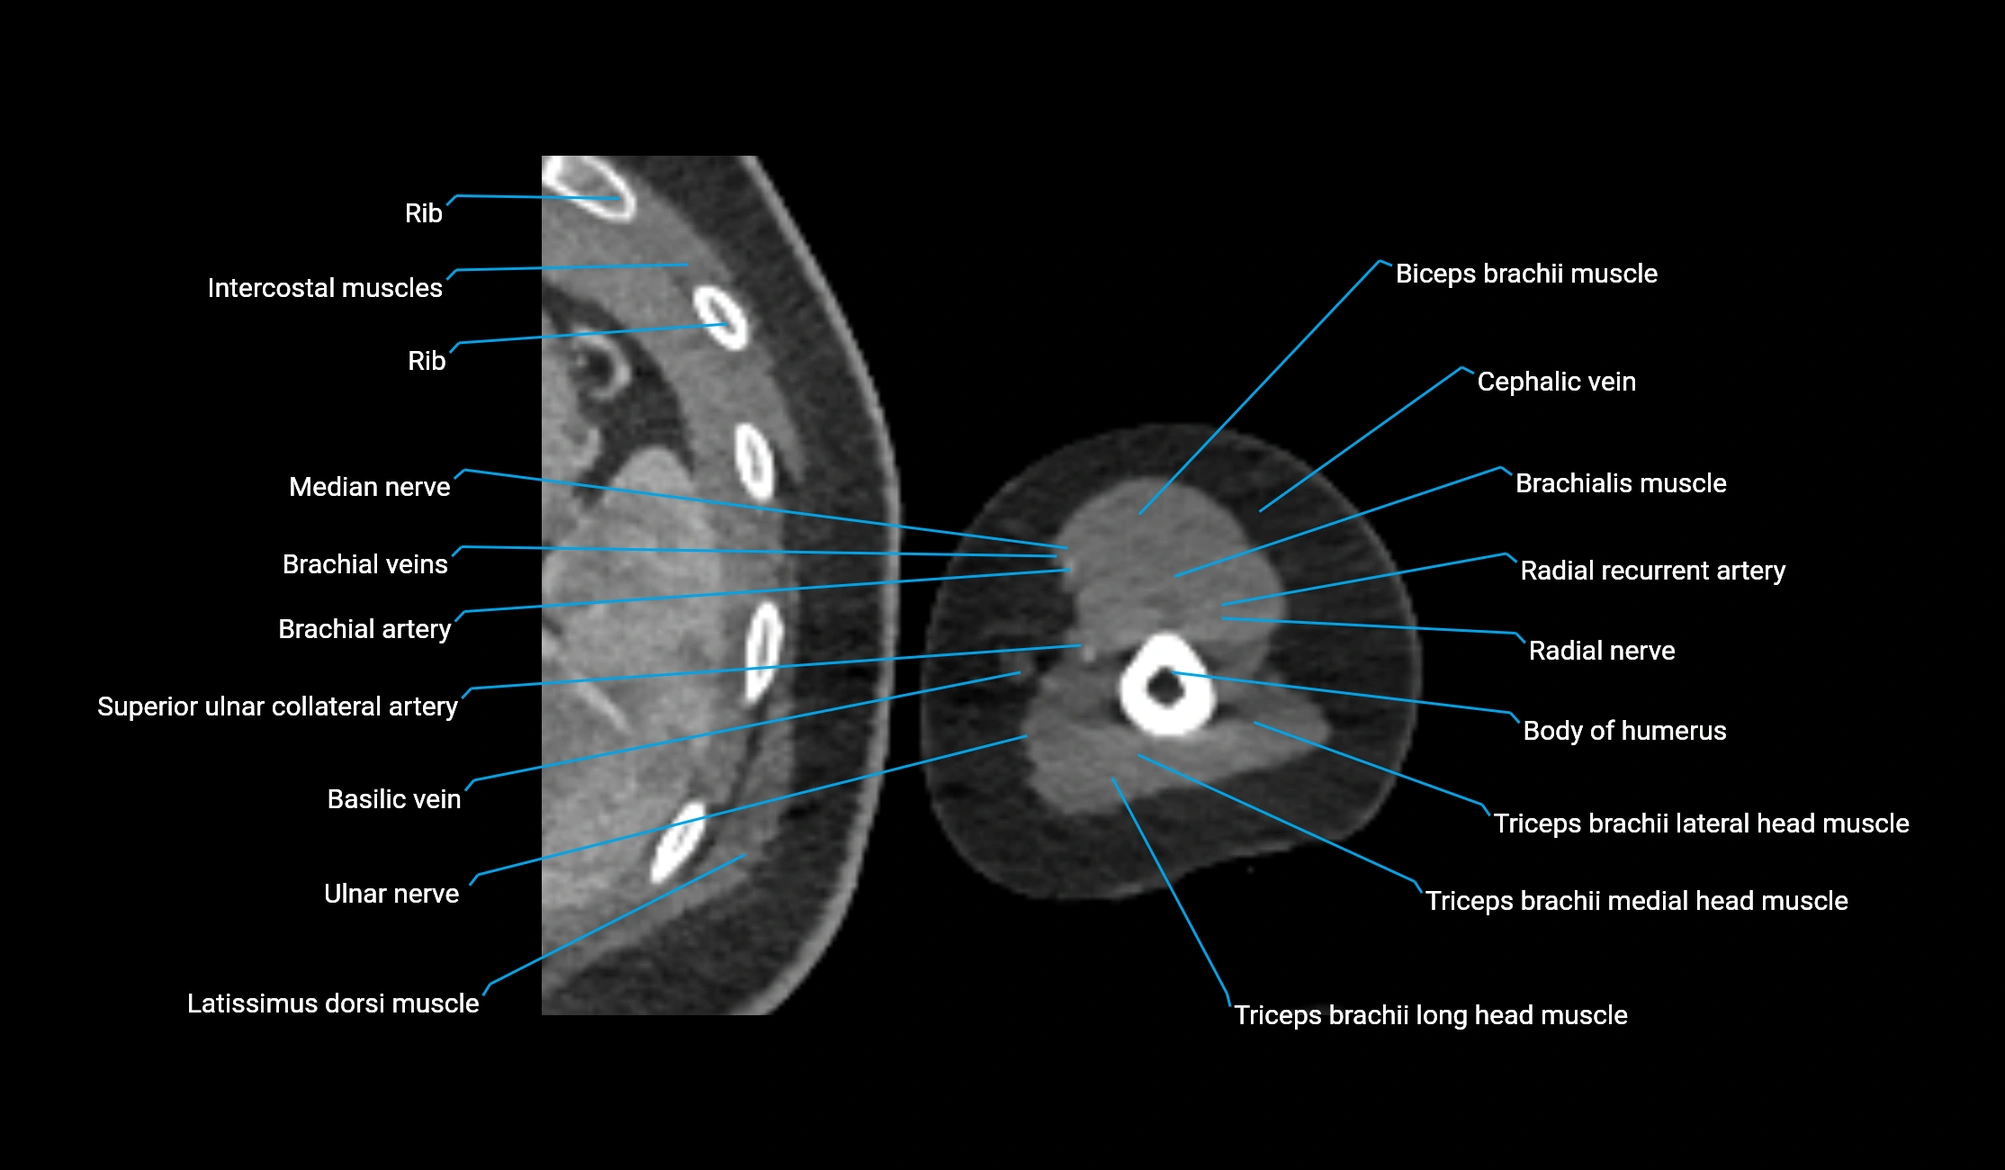

CT image